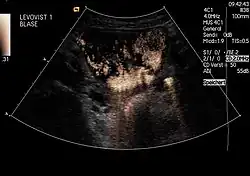

Um einen Rückfluss (Reflux) von Urin aus der Blase in die Niere auszuschließen: Diese Untersuchung, genannt Miktionsurosonografie (MUS), kann die bisher durchgeführte Röntgenuntersuchung mit Kontrastmittel (Miktionscystourogramm, MCU) ersetzen. Auf diese Weise ist also eine Refluxprüfung ohne Strahlenbelastung möglich. Da die empfindlichen Gonaden bei der Röntgenuntersuchung regelmäßig mit im Nutzstrahlenbündel liegen, ist dies ein großer Vorteil.

Um beim Jungen die Harnröhre mit darzustellen (da Jungen Harnröhrenklappen (Urethralklappen) haben können, Mädchen aber nicht), erfolgt die Erstuntersuchung beim Junge meist als klassisches MCU, Verlaufsuntersuchungen dann aber als MUS.